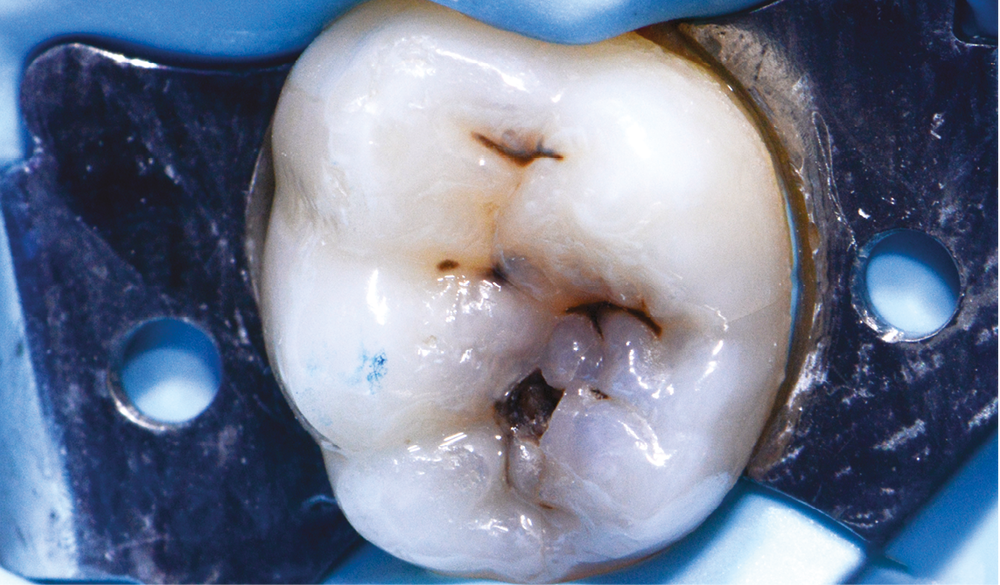

Cliniquement, deux types de lésions carieuses peuvent être observés : des caries actives et des caries chroniques à progression lente.

Dans le cas de caries chroniques, la surface de l’émail présente une zone blanchâtre, brunâtre ou noire. L’émail peut être brillant et paraître dur et lisse au sondage délicat le long de la surface. Sur les faces lisses, les lésions carieuses sont généralement situées à distance de la gencive marginale. Dans ce cas, le tissu dentinaire sous-jacent est brunâtre et plus dur.